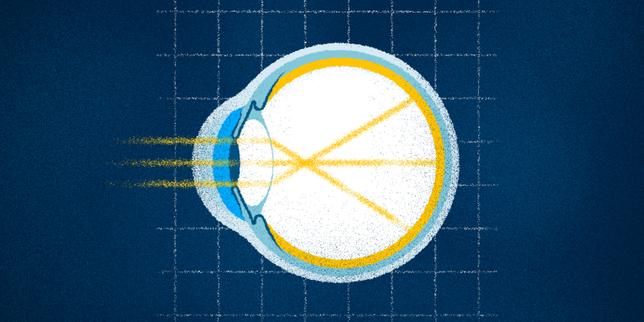

L'équipe a imagé les capillaires sanguins où se produisent les échanges gazeux entre le sang et les cellules.